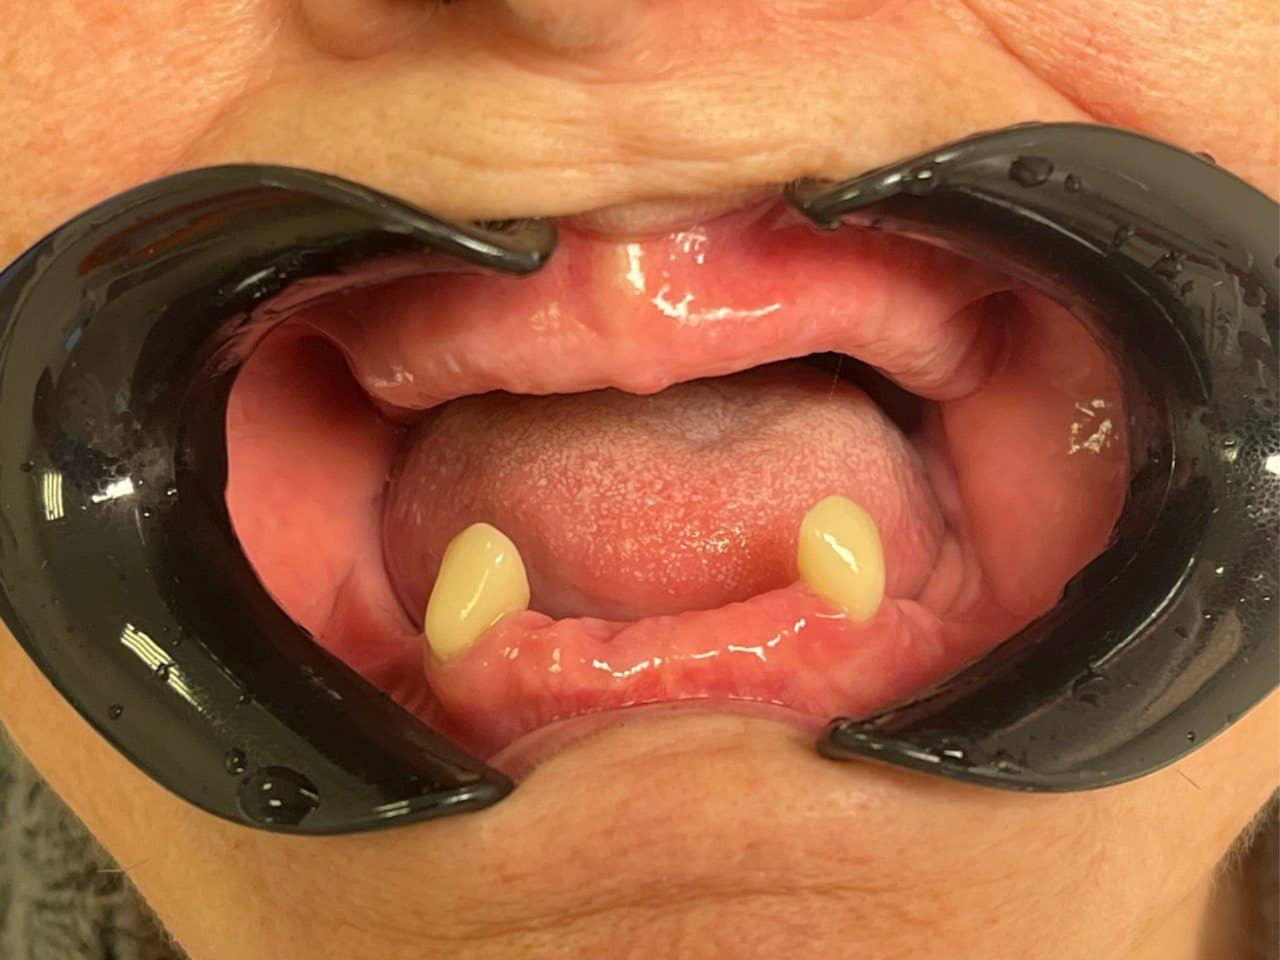

До

Клиническая ситуация

Пациент обратился в стоматологию «Забота» со следующими жалобами:

• отсутствие большинства зубов на обеих челюстях;

• невозможность нормально пережёвывать пищу — пациент питался преимущественно мягкой и перетёртой пищей;

• нарушение дикции — речь стала нечёткой из‑за отсутствия зубов;

• эстетический дефект — запавшие губы, изменение овала лица, стеснение при улыбке и общении;

• психологический дискомфорт — пациент считал, что «уже ничего нельзя сделать» и смирился с ситуацией.

Анамнез: зубы утрачивались постепенно в течение многих лет из‑за кариеса, заболеваний пародонта, отсутствия своевременного лечения. На момент обращения пациент не пользовался никакими протезами.

Клиническая картина

Челюсть

Состояние зубного ряда

Верхняя челюсть

Полное отсутствие зубов (полная адентия)

Нижняя челюсть

Сохранены только два клыка (зубы 3.3 и 4.3 — нижние клыки слева и справа). Остальные зубы отсутствуют.

Сохранённые клыки: устойчивы, без патологической подвижности, корни состоятельны. Именно они стали ключом к успешному протезированию нижней челюсти.